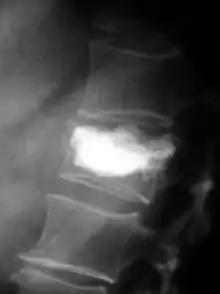

В оригінальній техніці, балонна кіфопластика являє собою дві канюлі діаметром близько 4 мм кожна. Балон вставляється (забивається) в місце перелому хребця. Наповнюючи повітряні балони контрастною речовиною, зламаний хребець частково випрямляється, але ціною зміщення здорової, цілої губчастої кістки . Випрямлені хребці фіксуються шляхом впорскування в створену порожнину кісткового цементу, який твердне протягом декількох хвилин і тим самим стабілізує зламаний хребець. На додаток до кісткового цементу в хребці можуть вставлятися інші імплантати, контейнери, стенти тощо.

Процедура проводиться в положенні лежачи під ренгтен-контролем. Операція частіше всього проводиться під загальним наркозом. Пацієнт вкладається на живіт, спину дезінфікують і накривають стерильними рушниками. Під контролем рентгенівського випромінювання, залежно від методики, одна або дві канюлі вводяться (забиваються) в тіло хребця через дуги хребців, потім внутрішню частину тіла хребця готують до імплантації матеріалу (зазвичай цемент на основі ПММА ). За звичайною процедурою вводять однин, або два балони, наповнені контрастною речовиною, для випрямлення та подрібнення навколишньої губчастої кістки. Утворюється велика за обсягом порожнина заповнена звичайним кістковим цементом. Тривалість операції: приблизно 20-40 хв.